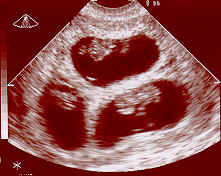

Çoğul Gebelikler 3 amnion, 3 koryonlu bir üçüz gebelikğin 8. gebelik haftasındaki ultrason görünümü)